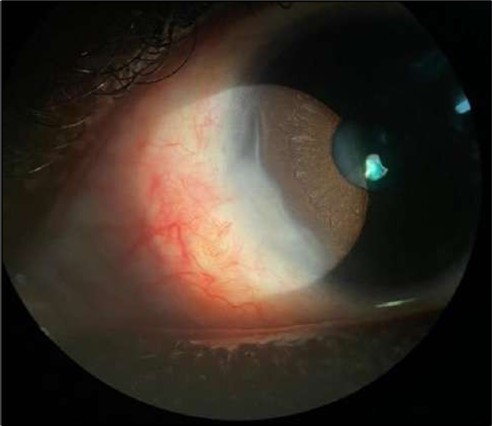

On the current presentation, Snellen VA was 6/6 in the right eye and 6/9 in the left eye, with normal IOP. The left eye demonstrated mild upper lid edema and intense nasal ciliary injection. Slit-lamp evaluation revealed a crescentic area of stromal corneal melting between 7 and 10 o’clock nasally, with overhanging edges and a fluorescein-positive base. No corneal infiltrates were present, and the surrounding stroma remained clear. The anterior chamber was deep and quiet, lens was transparent, pupil was round and reactive & normal posterior segment. Anterior segment optical coherence tomography (AS-OCT) confirmed a localized ulcer, measuring 1324 µm in horizontal width and extending to a depth of 380 μm, compared with an adjacent healthy corneal thickness of 824 µm, corresponding to approximately 46.1% stromal thinning (Figure 1a, Figure 1b, Figure 1c)

Figure 1a.Left eye (OS), on presentation. Slit-lamp image: crescent-shaped peripheral corneal ulceration located nasally, with severe adjacent conjunctival injection, peripheral thinning, and stromal infiltration.

Despite systemic and topical management over one month, the epithelial defect persisted, indicating refractoriness to medical therapy. OCT imaging showed ulcer depth reduction to nearly 42% stromal thinning and width of 1180 µm, highlighting partial corneal healing. In view of the persistent ulcer and ongoing local inflammation, a conjunctival resection was performed to excise the perilimbal inflammatory focus and promote corneal repair Figure 3a and 3b.